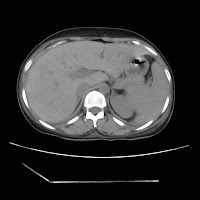

(HRCT)CT-Scan investigation done on 19Aug15 :

Series3